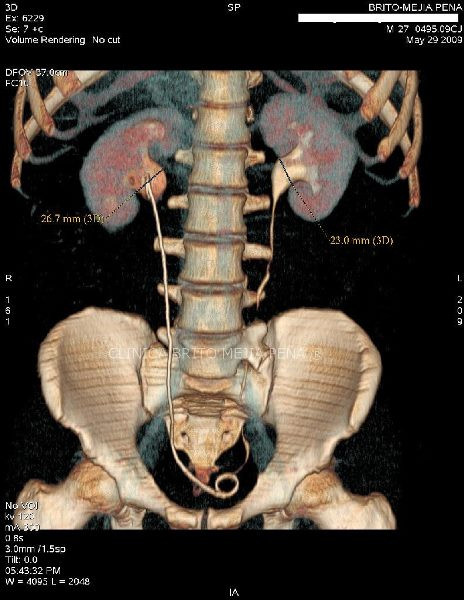

Urotac 3D

Post Image